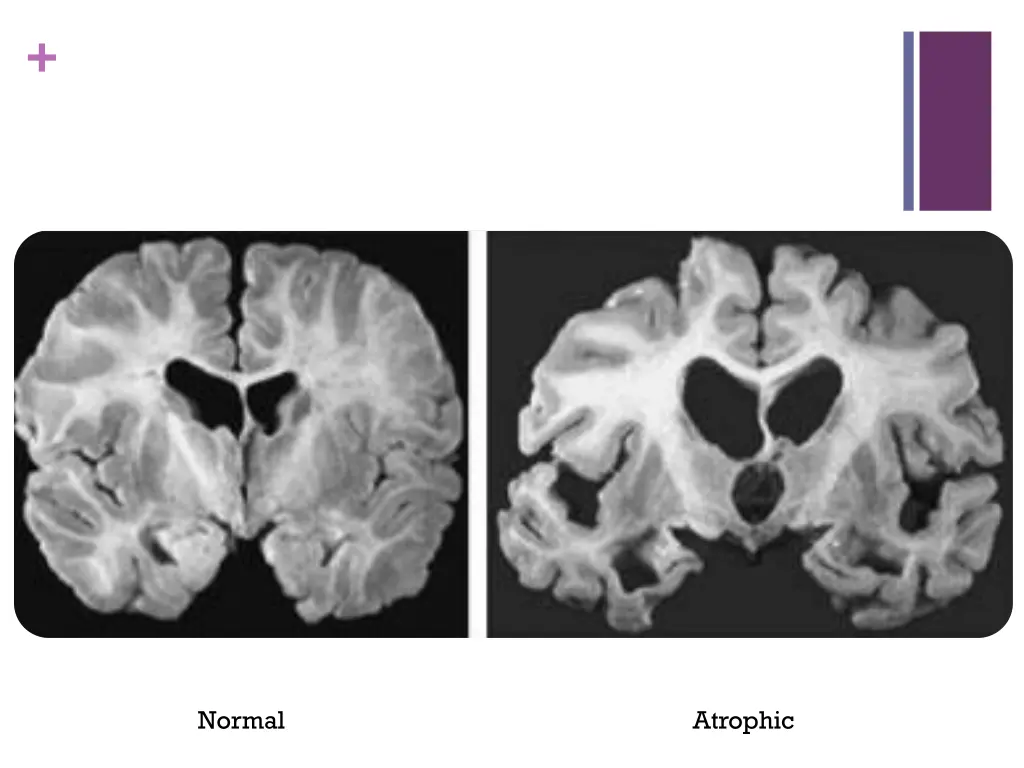

+ Normal Atrophic

+Diagnosis Diagnosis is clinical Rely on history and cognitive/neuropsychological assessments that demonstrates a slowly progressing cognitive disorder which causes impairments in daily life. Brain structure on MRI may demonstrate medial temporal atrophy bilaterally PET scans can demonstrate decreased metabolism in temporal and parietal regions Cerebrospinal fluid might show low Amyloid beta, and elevated Tau (not specific)